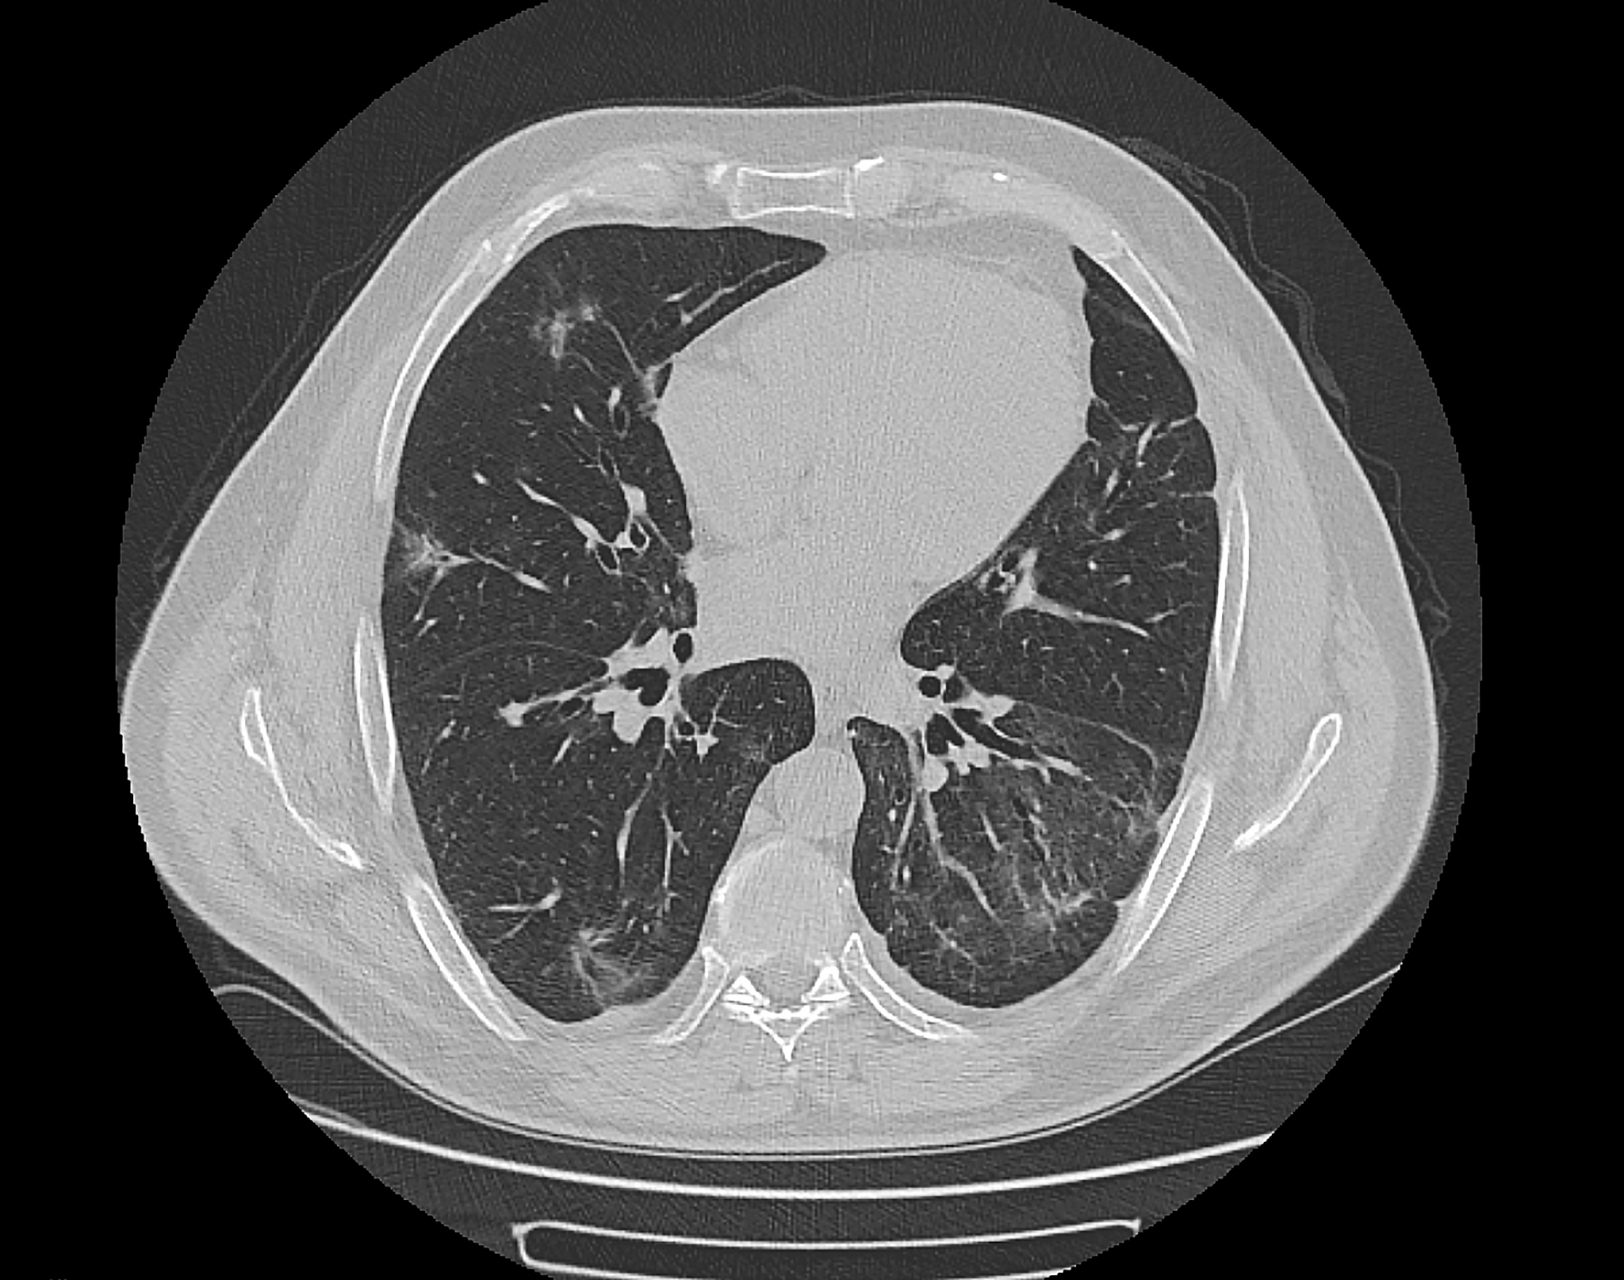

在检测肺部结节时,高分辨率计算机断层扫描是目前最清晰,最敏感的影像

双肺弥漫粟粒状结节影请各位大神分析